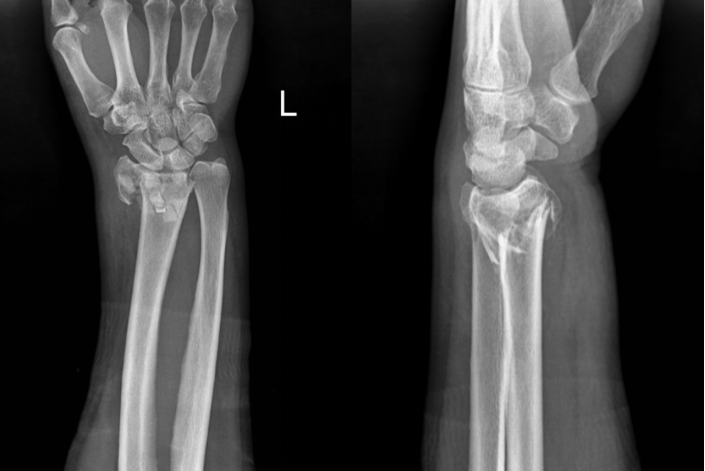

艾先生被送至重庆长城骨科医院急诊科后,医护人员立马着手查体、拍片,最终诊断其为桡骨远端骨折。

(▲X光片清晰可见艾先生左桡骨远端粉碎性骨折。)

该院手显微外科中心急诊组组长任俊成医生介绍道:“人在跌倒时常习惯性地用手掌或手背撑地,该部位为松质骨和皮质骨的交界处,较为薄弱,因而桡骨远端骨折在临床发生率较高,且多发生于骨质疏松的老年人。”